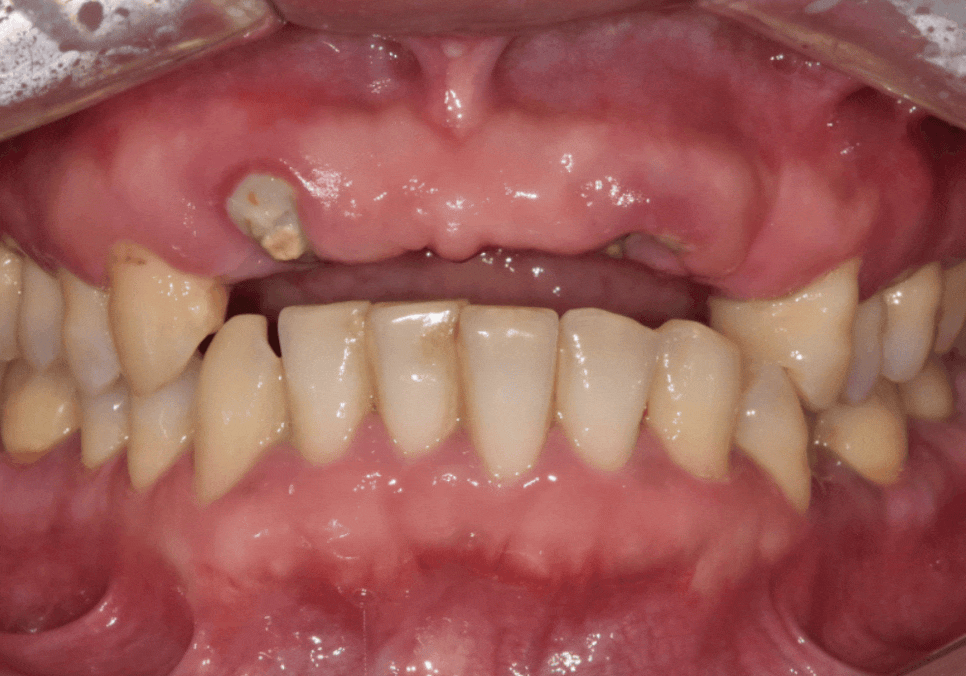

앞니 브릿지 부러짐

얼마 전 저희 치과를 찾으신 환자분의 사례예요.

3년 전에 타 병원에서 진행한 앞니 브릿지가

통째로 부러져서 저희 치과를 찾아주셨는데요~

입안을 살펴보니 ...

브릿지를 지탱하던 치아 2개(#12, #22)가

잇몸 안에서 완전히 부러져

뿌리만 간신히 남아있는 상태였습니다.

"뿌리가 남아있으니

다시 살려서 쓸 수 있지 않을까요?"

자연치를 살려서 쓰고 싶은 환자분의 마음,

저도 충분히 이해합니다.

하지만 건물도 기둥이 튼튼해야 무너지지 않듯,

보철물도 마찬가지예요.

지금 남아있는 뿌리는 단 두 개인데,

이 약해진 기둥 두 개가

다섯 개의 치아(#12, 11, 21, 22, 23)가 받는

엄청난 하중을 전부 견뎌내기에는

사실상 한계가 있었습니다.

쉽게 말해...

몸집에 비해 다리가 너무 부실한

'상체 비만'형 구조라고 생각하시면

이해가 빠르실 거예요.

억지로 다시 만든다 해도 머지않아

또 부러질 위험이 너무 높았죠.

환자분의 장기적인 치아 건강을 위해,

고심 끝에 발치 후 임플란트로

진행하실 것을 권해드렸어요.